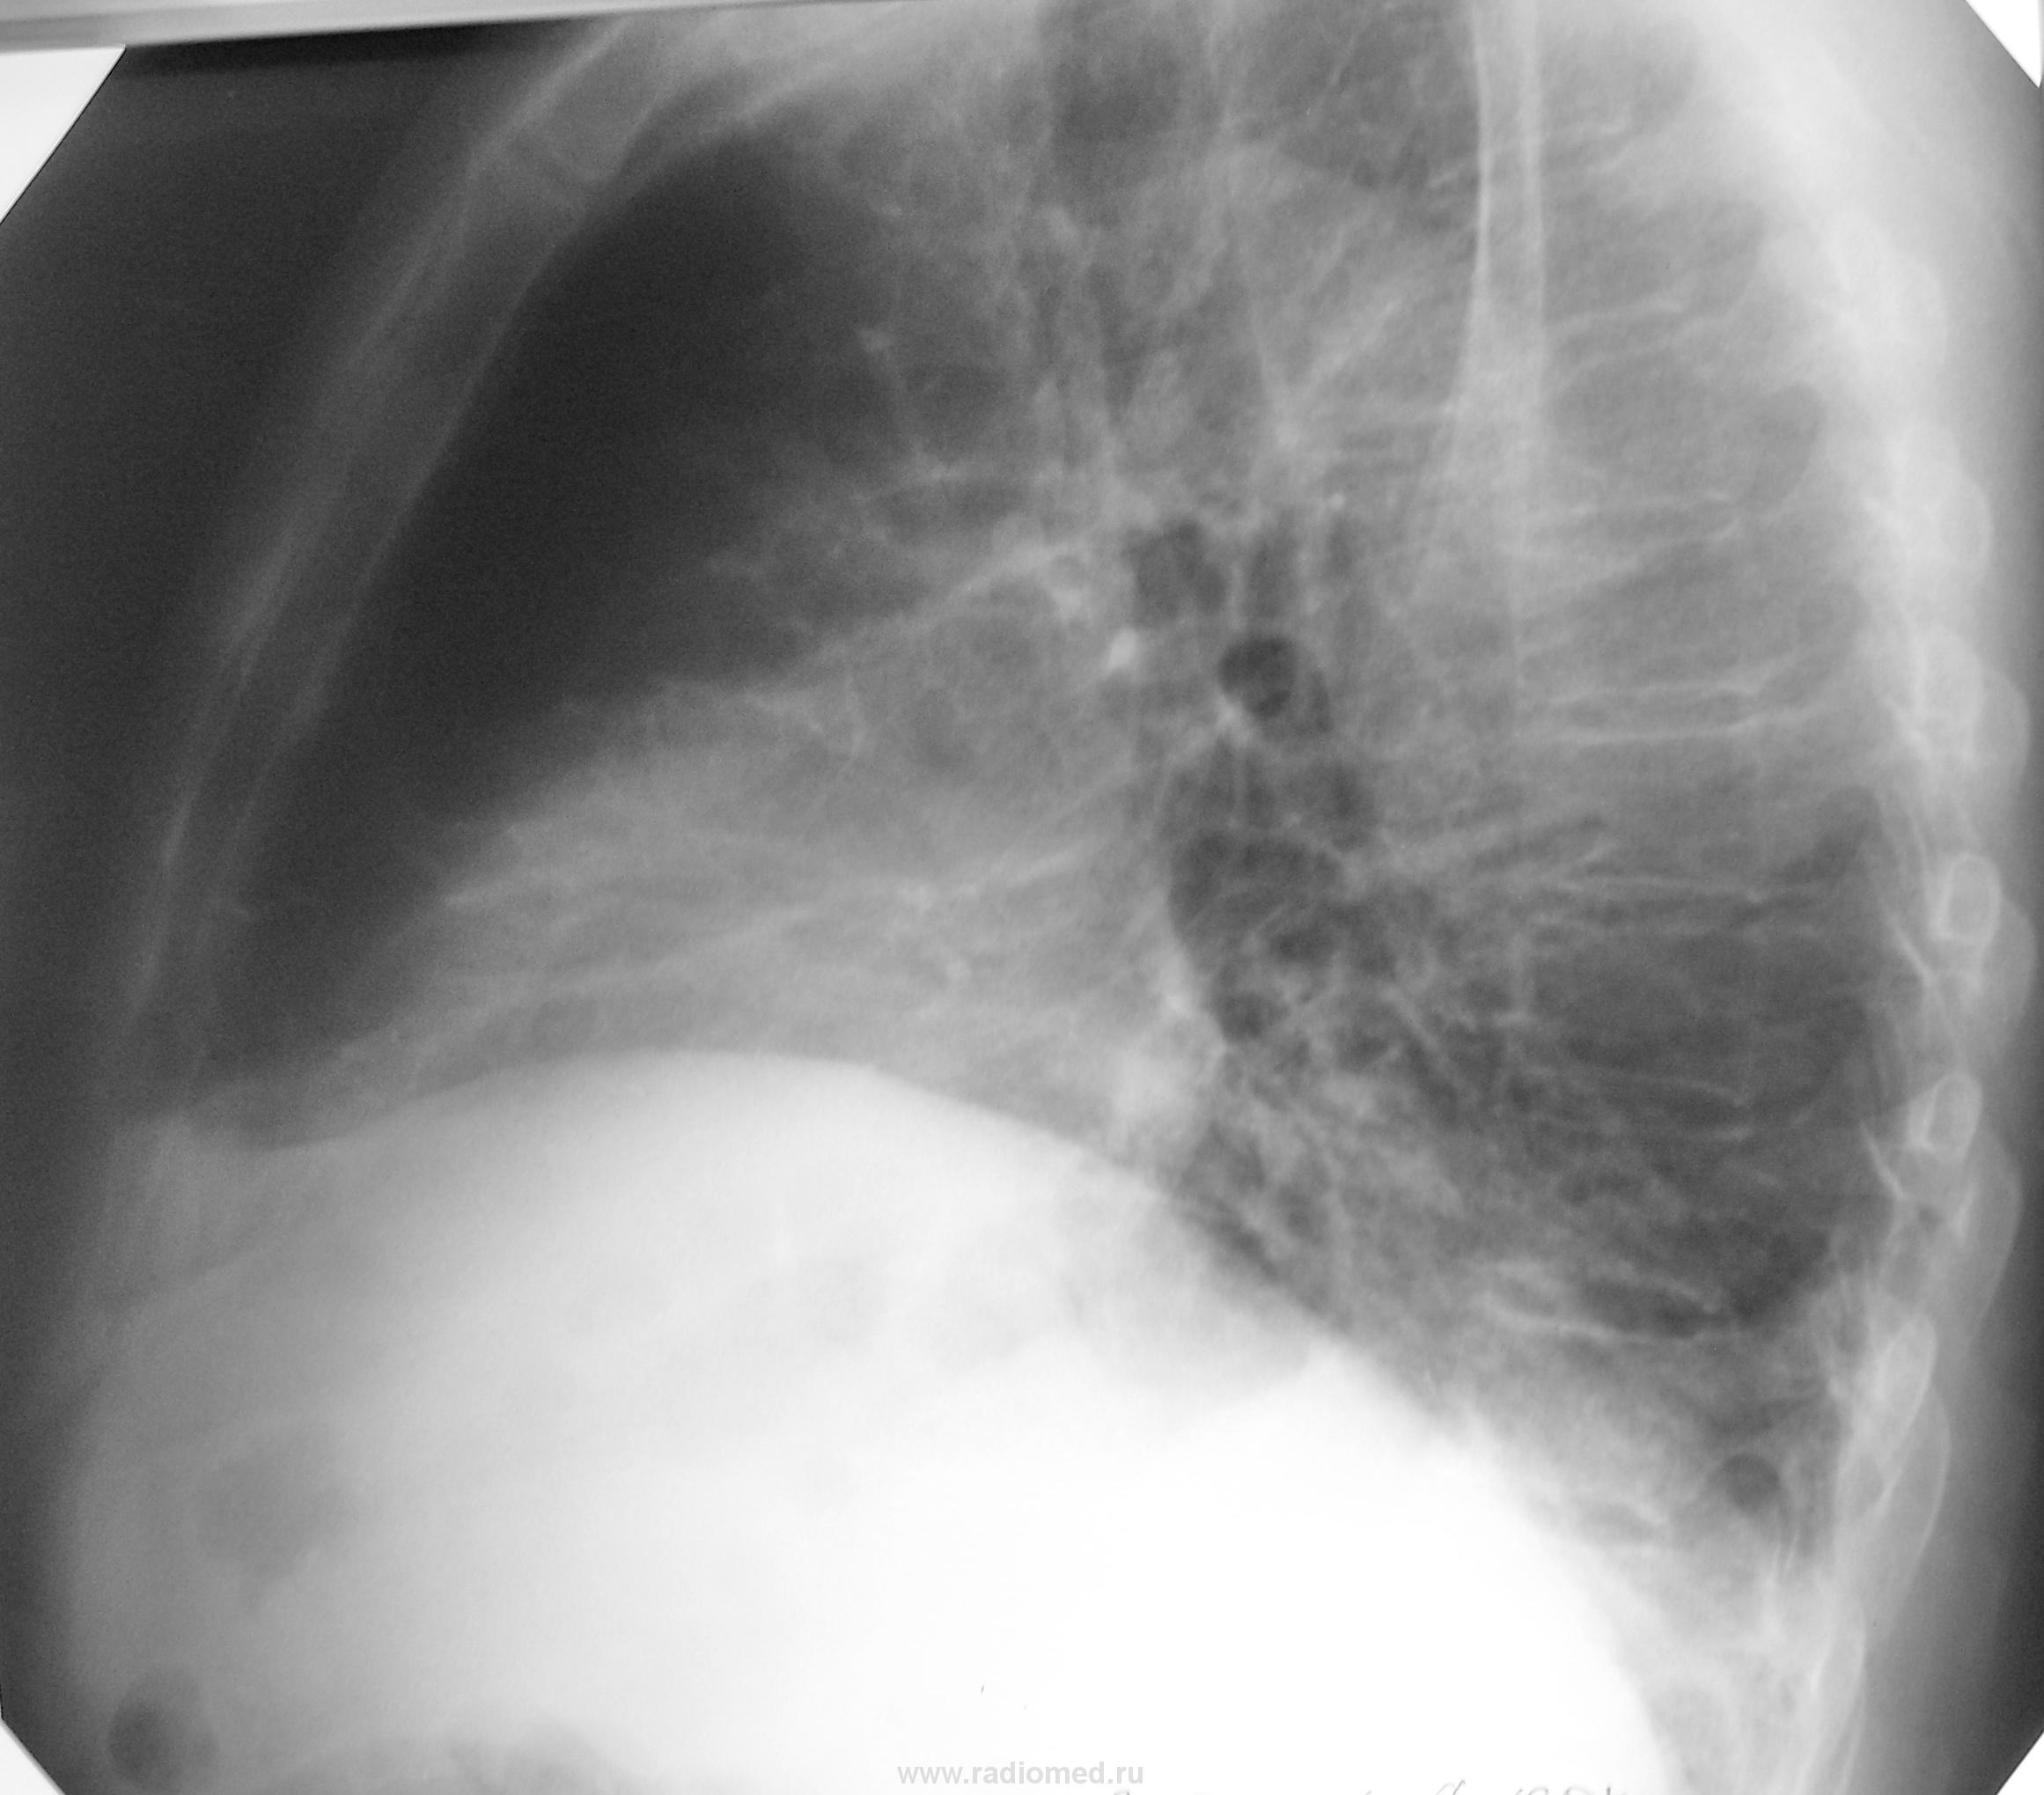

На проф. осмотр пришли двое дедушек. Обоим около 75 лет. Жалоб никаких не предъявляют. С их слов, никогда ничем не болели. Решили съездить в санаторий.

У первого левый купол диафрагмы просто поднят, а у второго похоже на начинающийся центральный рак справа.

По моему в 1м случае левосторонний базальный плеврит, во 2м левый купол деформирован, уплощен.

мне тоже в 1м случае левый синус не нравится, есть возможность узи плевральных полостей сделать?архив?

Облитерация реберно-диафрагмального синуса слева. Левое легкое полностью не расправлено.Справа компенсаторная эмфизема.

А  что за небольшой кругляш на уровне переднего отрезка 3 ребра слева в 1-м случае?

Кругляшом обычно называют округлый фокус, а тут кольцевидная тень. По моему сосудистый компонент, суммация теней.

1).Эта округлая тень видна и на боковушке.... сосудистое происхождение-не факт,хотя могет ортогональное сечение,тем более близ корня.Выпота по боковому не видно-запаян синус-старые дела...мало ли что больной говорит.Загляните к нему в паспорт-он и сам забыл что у него было (Отвлекусь: смотрела мужик,-лечили его несколько месяцев неврологи от межреберной, пока не додумались снимок сделать.Отправили в стационар с пневмонией.По снимку мне(!) не понятно.Беру скопически- 4 сломанных ребра кряду и плевра утолщена локально,а мужик пяткой в грудь,что не ломал...Вот и слушай больных)

2).Про начинающийся центральный-круто!По-моему сосуд широковат.А вот верхушка слева:деформация рисунка и тени-апикально плотная(кльцинат?)и еще тенюшки...к сожалению,разобрать не могу.Деформация  левого купола диафрагмы,плевра паракостальная утолщена,периплевральные наложения и спайки-тож старые песни.Я бы сравнила с предыдущими снимками(если есть такая возможность) на предмет теней в S1 слева